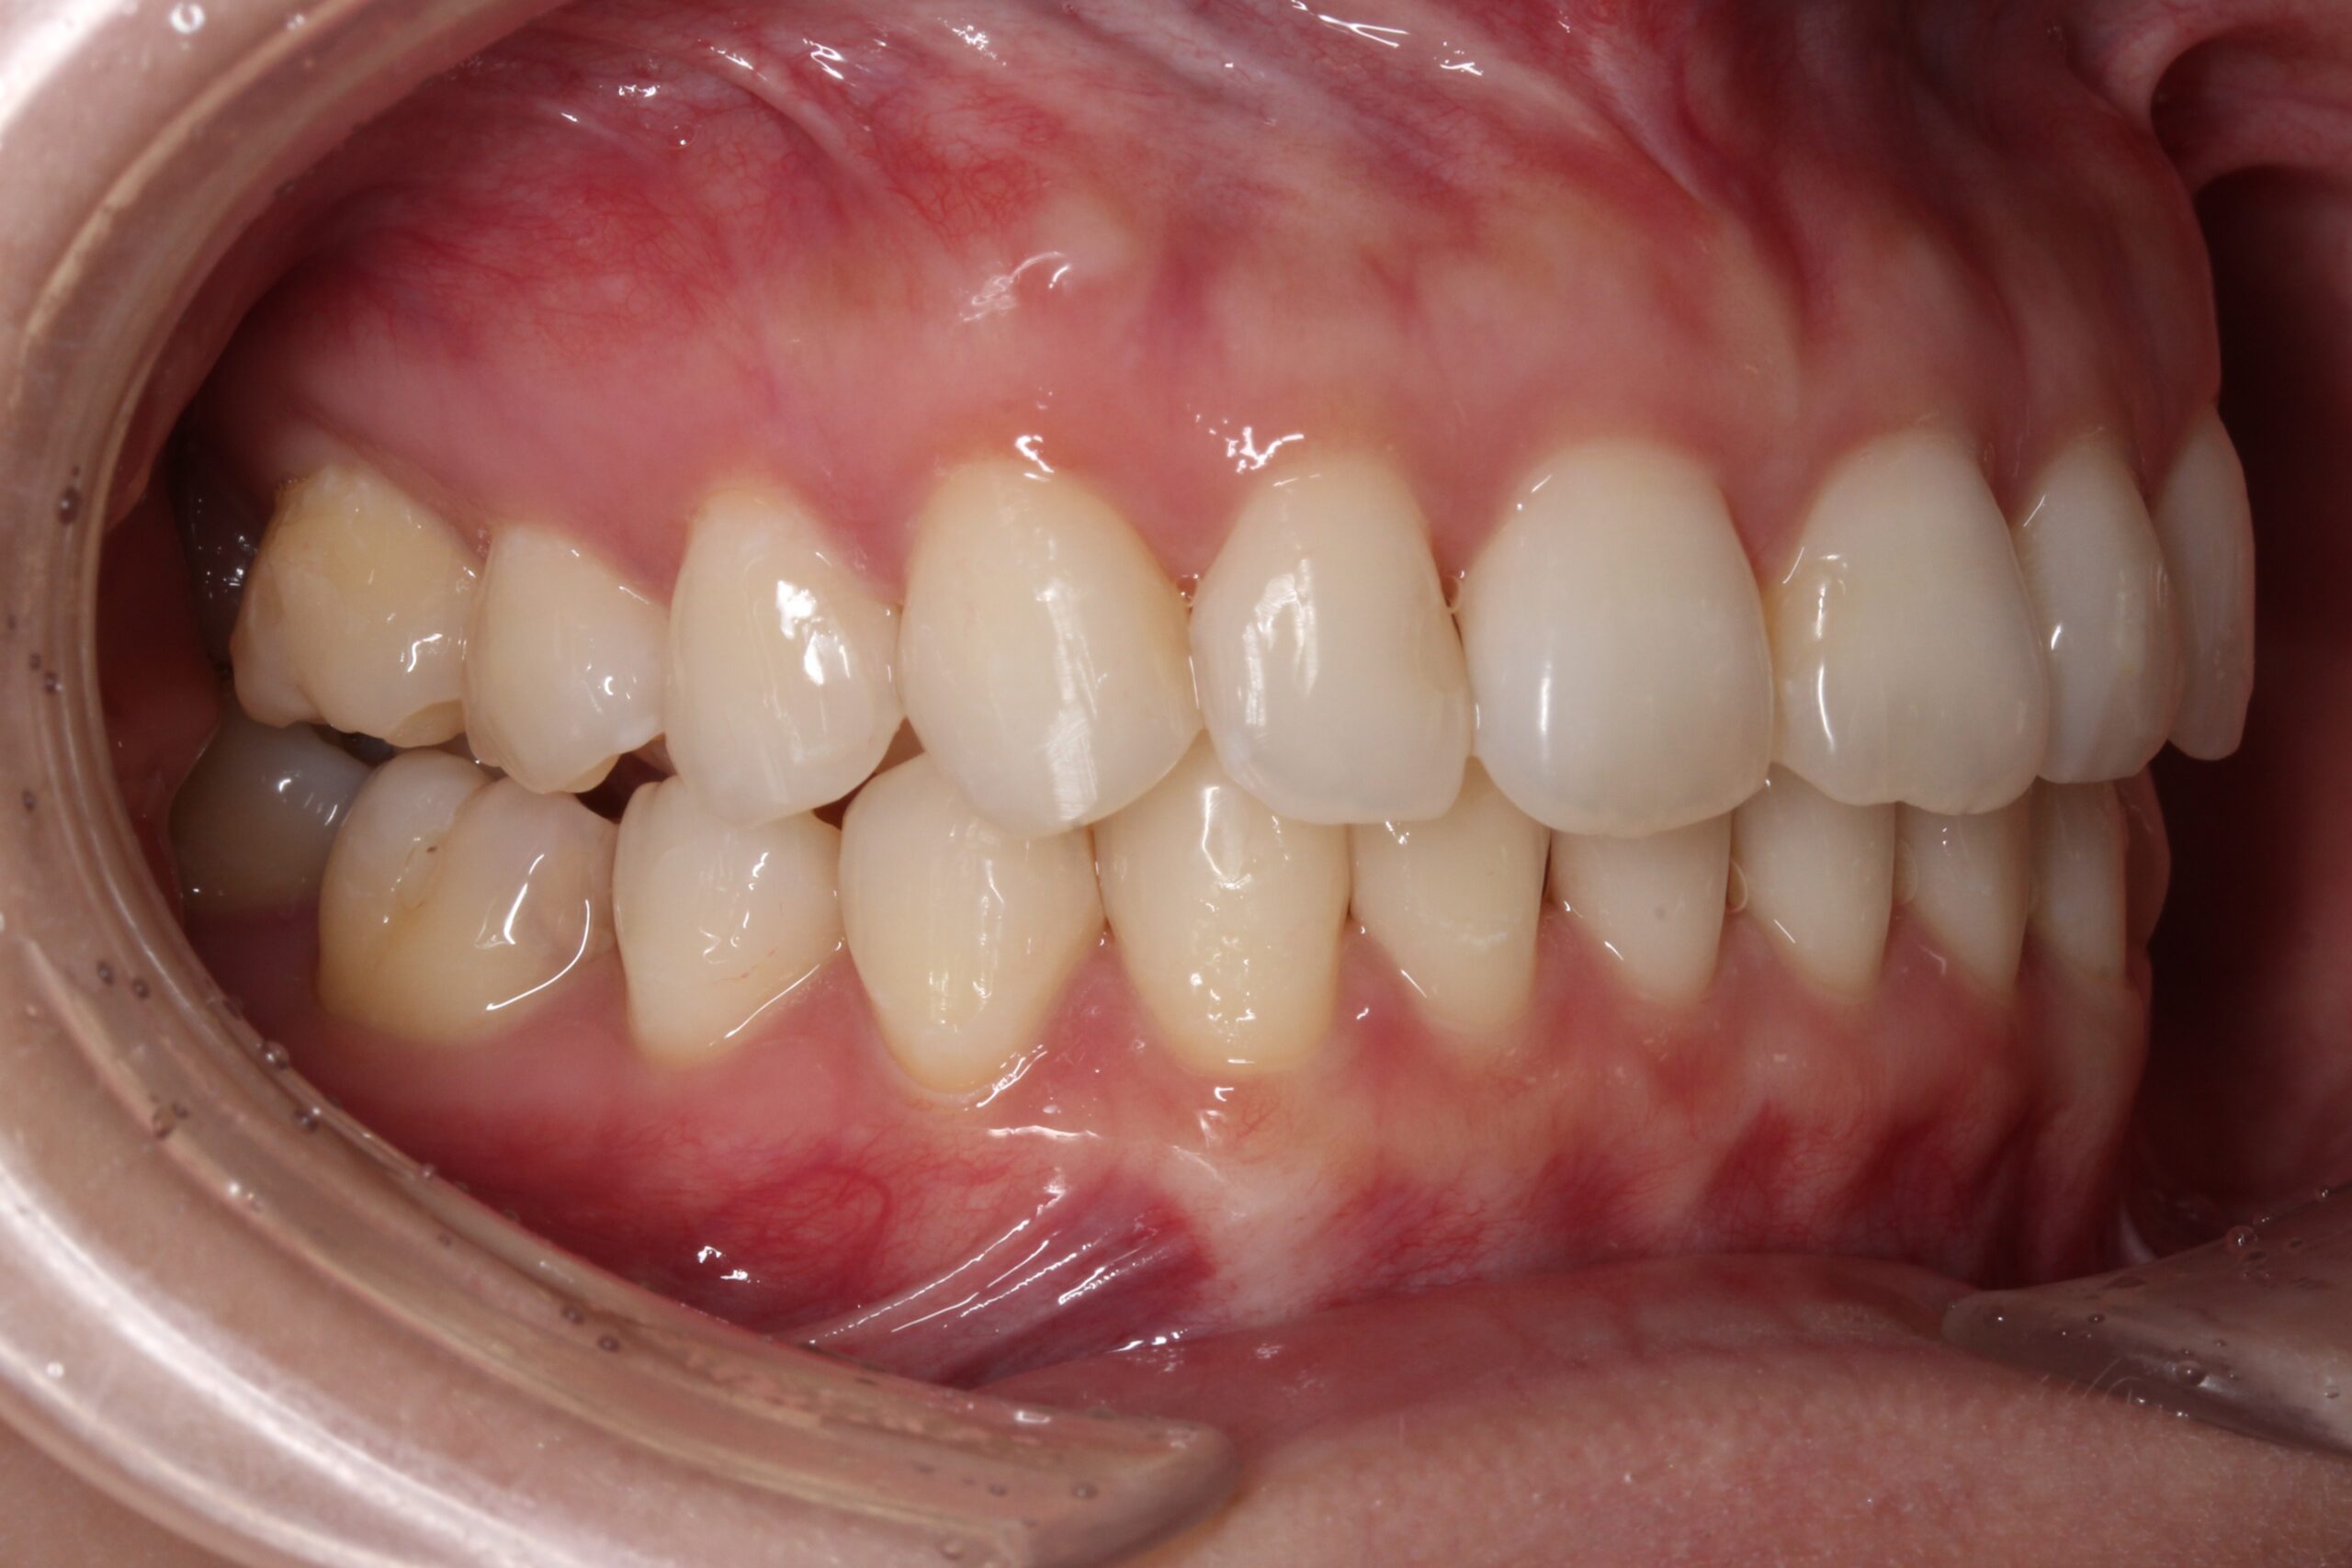

矯正術前:左側

矯正術後:左側